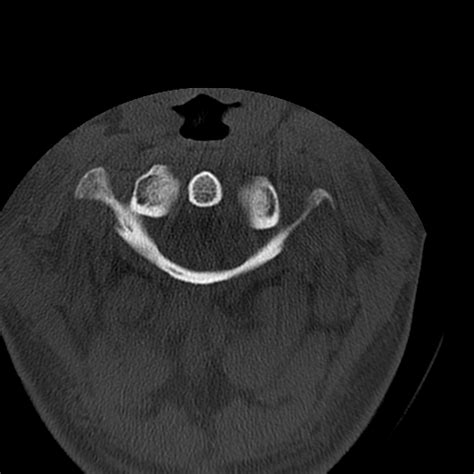

• Computed Tomography (CT) Scan: This is the gold standard for diagnosing occipital condyle fractures. CT scans provide detailed images of the bony structures and can help identify the location and extent of the fracture.

Classification of Occipital Condyle Fractures

Occipital condyle fractures are classified based on their pattern and mechanism of injury. The most commonly used classification system is the Anderson and Montesano classification, which categorizes these fractures into three types:

Understanding the type of fracture is essential for determining the appropriate treatment plan.